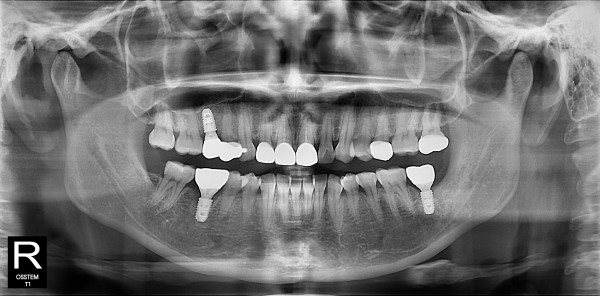

사랑니발치 30대/여성

5e20e086184bc11a2d853605b7813944_1764319714_7286.jpg